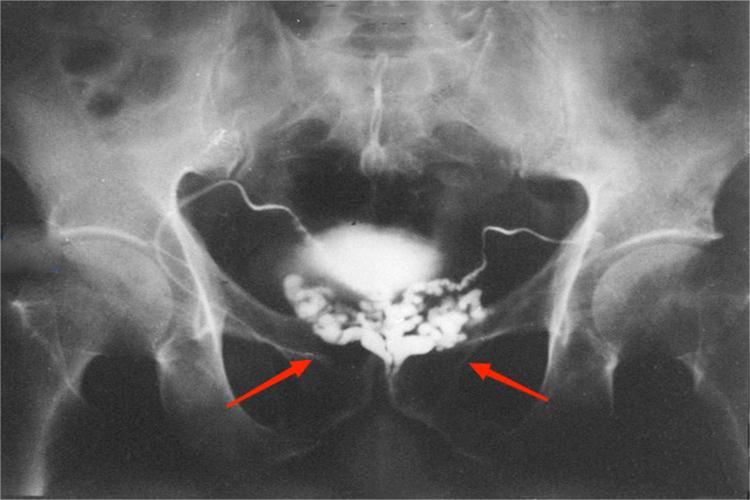

精囊位于前列腺上方,膀胱之后,对称卵圆形,与膀胱后下壁之间有脂肪组织间隔。CT表现为平扫精囊呈八字形均匀软组织密度影,在周围低密度脂肪组织的衬托下显示清楚,精囊周围的静脉丛显示为点状、条索状的软组织影。精囊前缘与膀胱后壁之间的精囊角为脂肪间隙,CT上为低密度影,增强无强化。